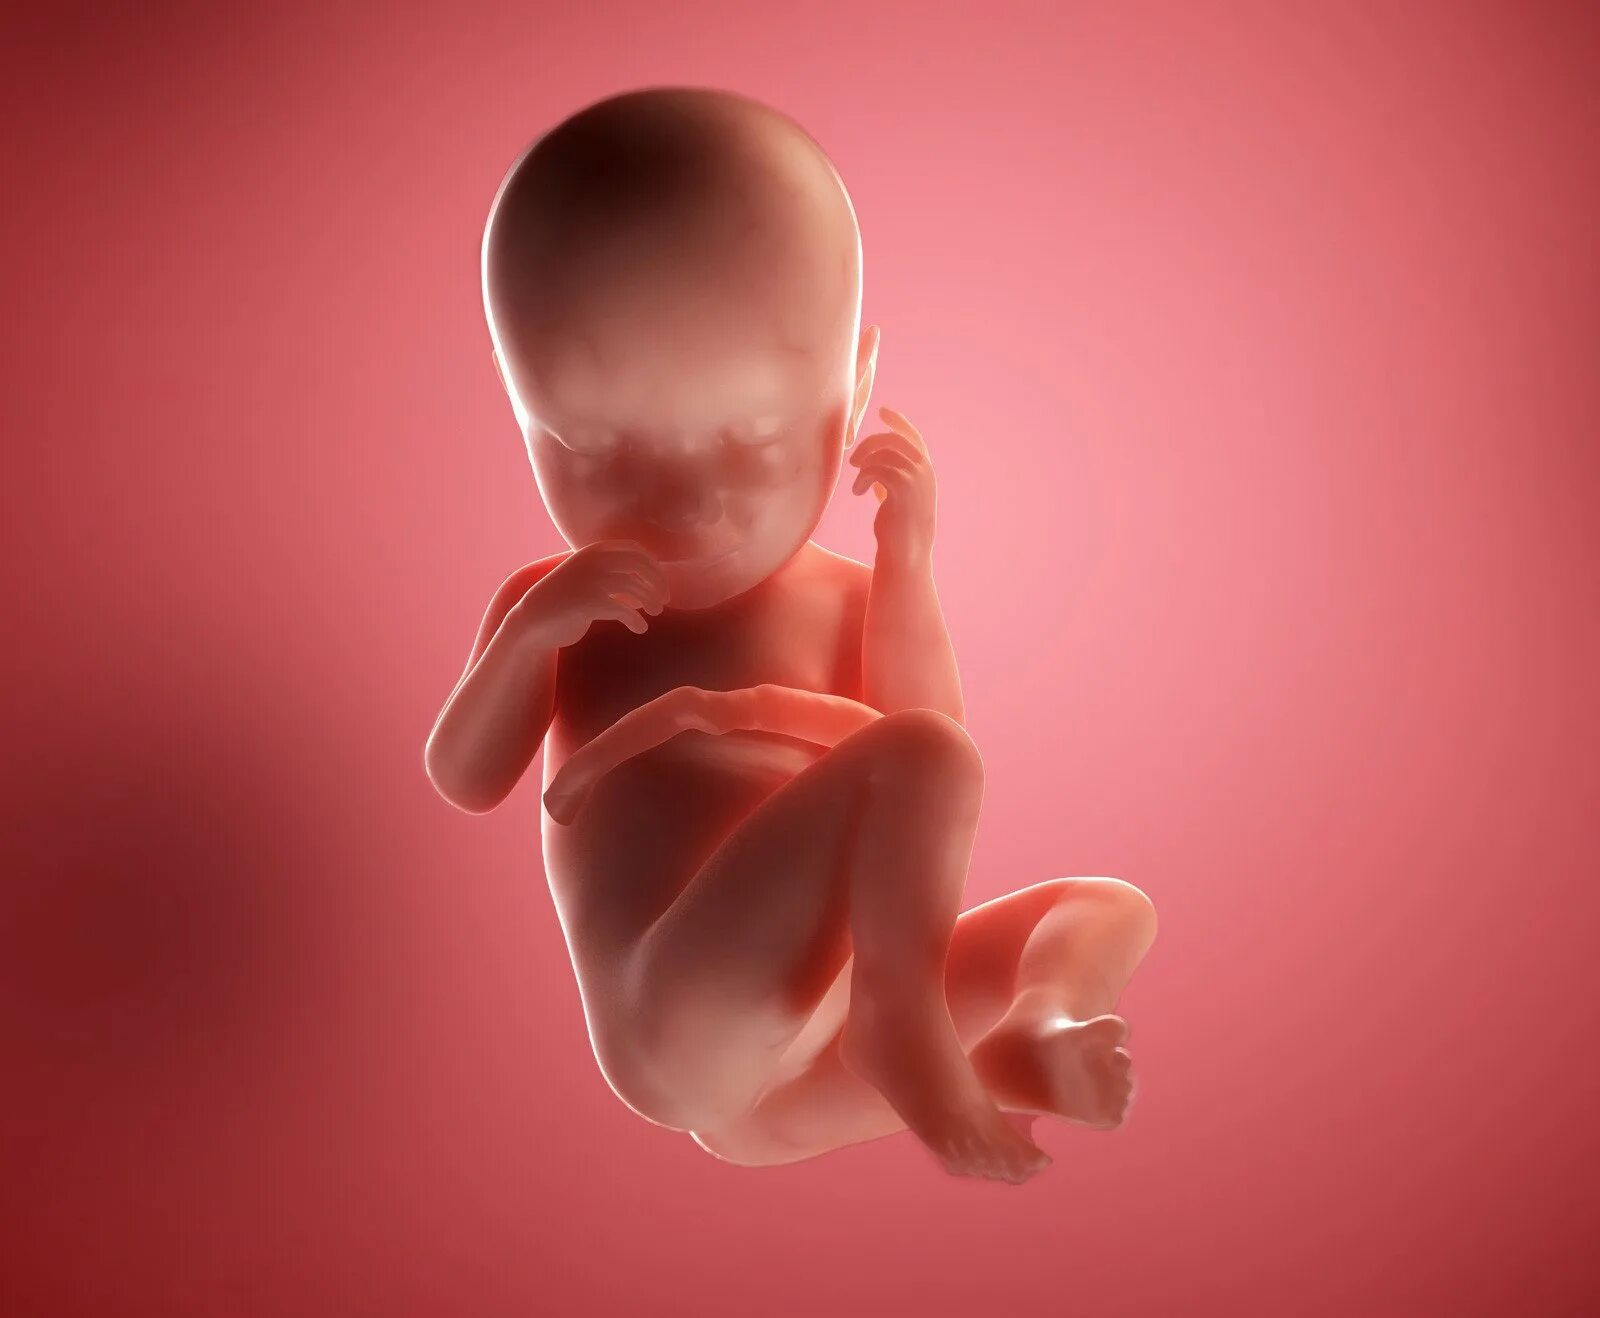

Как выглядит ребенок в 22 недели